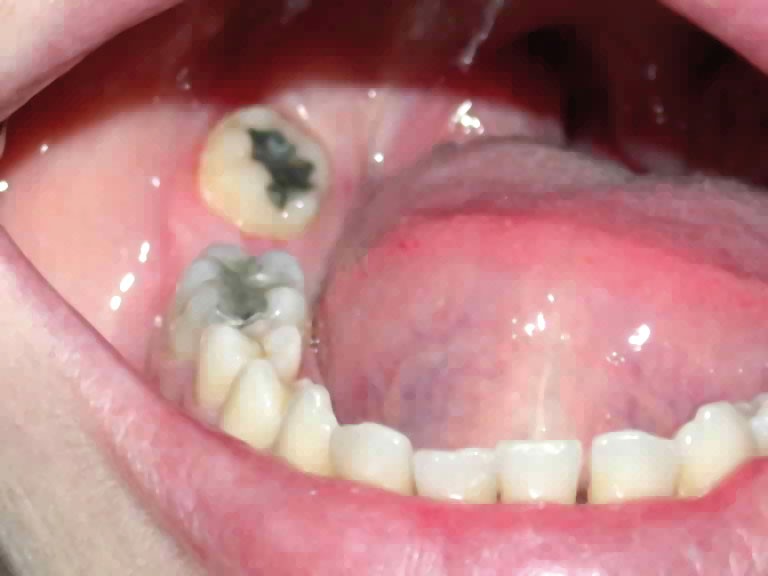

• anomalie de la forme d’arcade maxillaire, 47, 18 et 28 sont absentes. (fig. 1 à 8), 48 est positionnée très postérieurement, quasiment au niveau de la branche montante (fig. 9 et 11).

Après assainissement parodontal, un traitement par expansion maxillaire avec vestibuloversion des incisives supérieures et mésialisation de 48 en lieu et place de 47 a été choisi. Il a été décidé d’extraire 38. Afin de permettre une reconstitution prothétique pour compenser la microdontie de 12 il est prévu de laisser un espace de part et d’autre de celle-ci, équivalent au diamètre mésio-distal de 22 soit 6,5 mm.